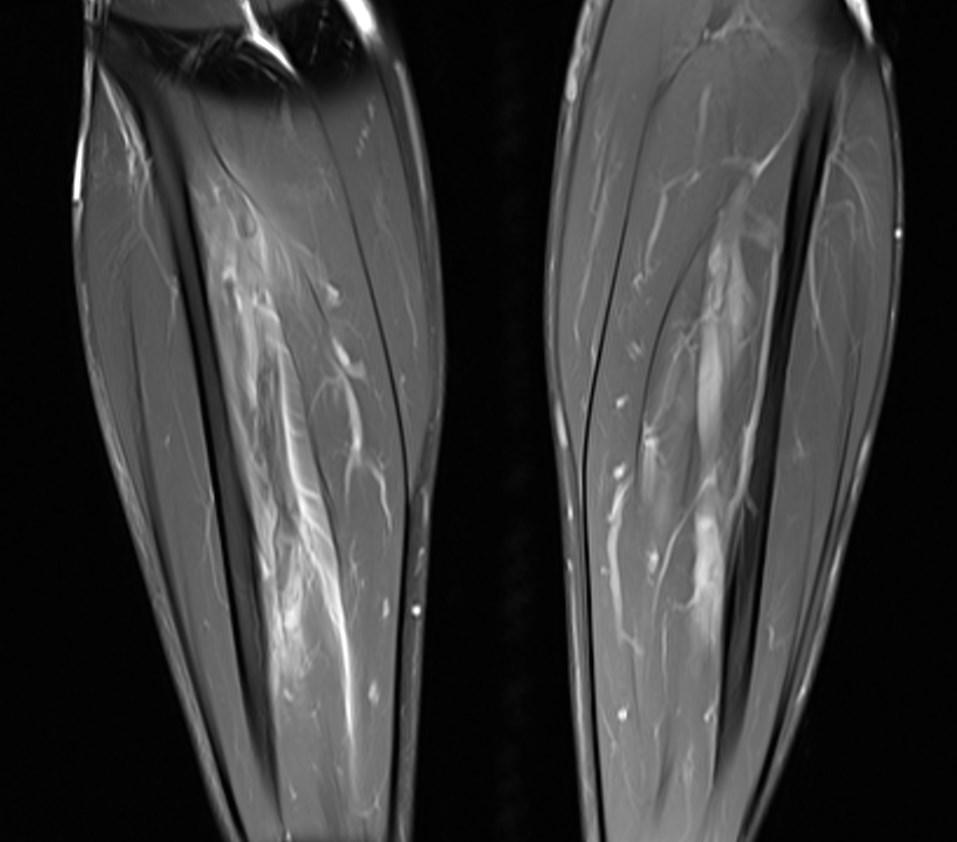

*29-year-old male present with pain in the right lower extremity for 3 days.

What is the most likely diagnosis?

Answer: Crural deep vein thrombosis

MR images showed perivascular edema, perifascial edema and the deep crural venous filling defects.